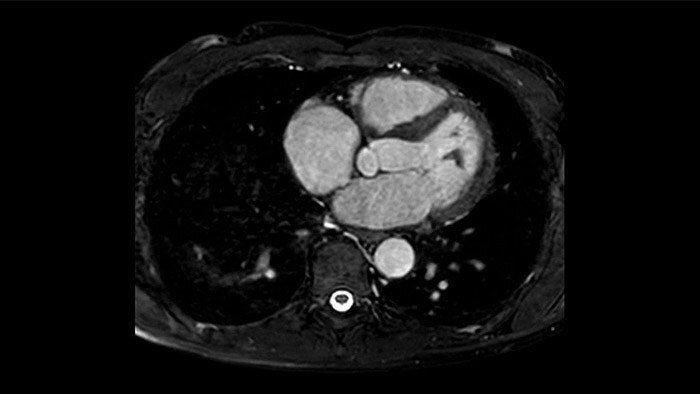

La utilidad diagnóstica y pronóstica de la RM cardíaca está aumentando. Evaluar la anatomía y función del corazón mediante adquisiciones cinematográficas, adquirir información sobre perfusión y viabilidad del tejido cardíaco, visualizar posibles edemas con secuencia de sangre negra, acceder e incluso cuantificar la caracterización tisular con CardiacQuant.